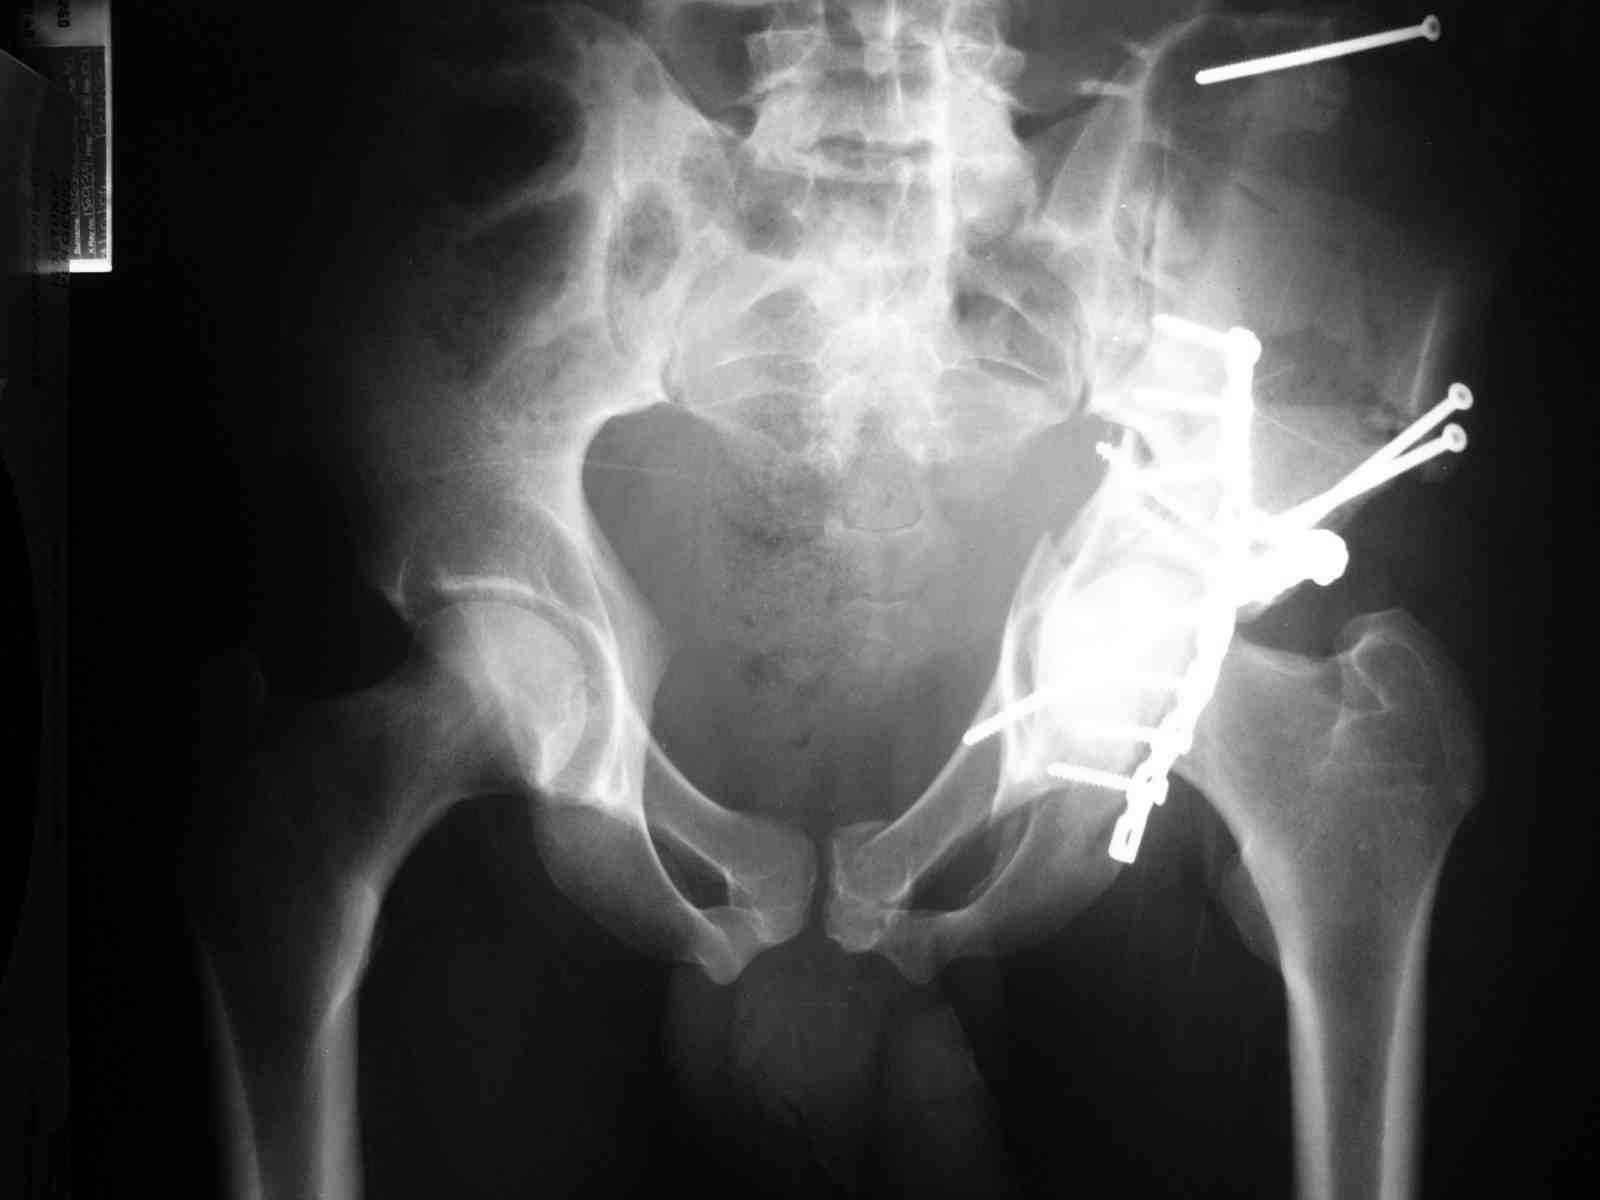

Уважаемые коллеги,43 летний мужчина, попав в автоаварию 13.10.2004, получил оскольчатый перелом обеих колонн левой вертлужной впадины.

На рентгенограммах - высокий двухколонный перелом вертлужной впадины с нарушением конгруэнтности, имеется обратная клиновидность суставной щели.

Спасибо за комментарии и рекомендации. Откровенно говоря, больного я прооперировал на прошлой неделе, через 5 дней после аварии и проблем с ним пока никаких нет, на удивление при достаточно обширной диссекции (илиофеморальный доступ) болей практически нет, так что больной самостоятельно садится в кровати, выполняет активные движения в оперированном суставе, сгибая до 60 градусов пока, далее с ассистенцией.

Причиной обращения к сообществу были возникшие непосредственно после операции сомнения и разочарования полученным качеством репозиции: а надо ли было трогать перелом вообще, репозиция передней колонны технически была очень сложна для меня, хотя реконструкции была в той же последовательности, что Д-р А.В.Рунков рекомендовал, в какой-то момент безуспешных манипуляций стал думать о *вторичной конгруэнтности*, которую не так давно обсуждали на

форуме и скелетном вытяжении. С репозицией и фиксацией задней колонны и отдельно задне-верхней стенки впадины проблем не возникло. Послеоп. Рг граммы в приложении. Если возникнут какие-либо дополнения или поправки - был бы признателен.